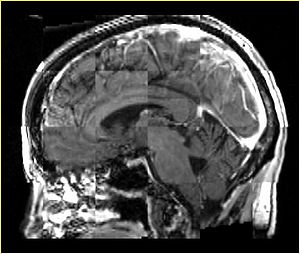

Qualitative assessment

BRAINSFit

A distinctive feature of BRAINSFit tool is the ability to automatically detect head region of interest, which is used for collecting intensity samples during metric calculation. Below is the overlay of such ROI in light blue overlayed with the image for Case10. This functionality appears to work consistently for all the cases used in the comparison.